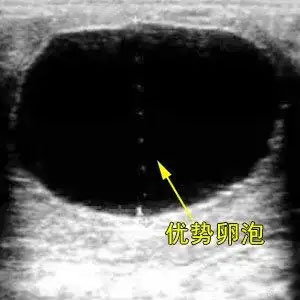

马匹繁殖就像一场精心策划的约会,而卵泡直径就是这场约会的时间表。母马的卵泡从米粒大小长到乒乓球那么大,整个过程藏着繁殖成功的关键密码。比如在发情周期里,卵泡会经历……